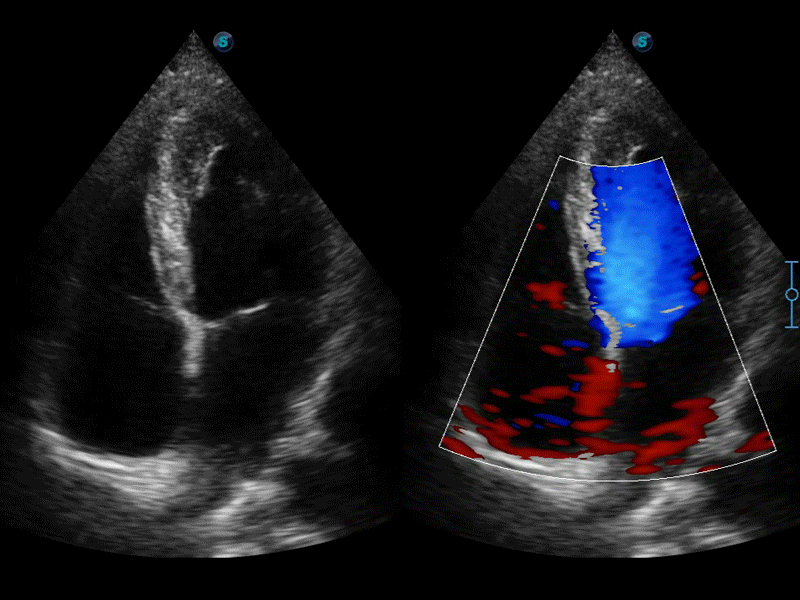

高分辨率血流成像技術(shù)提高了對低速血流信號的檢測能力。在提高空間分辨率的同時,也克服了血流外溢現(xiàn)象,為用戶提供更加真實的血流動力學(xué)信息。

自動識別收縮和舒張末期心肌內(nèi)膜,自動計算射血分?jǐn)?shù)EF值。